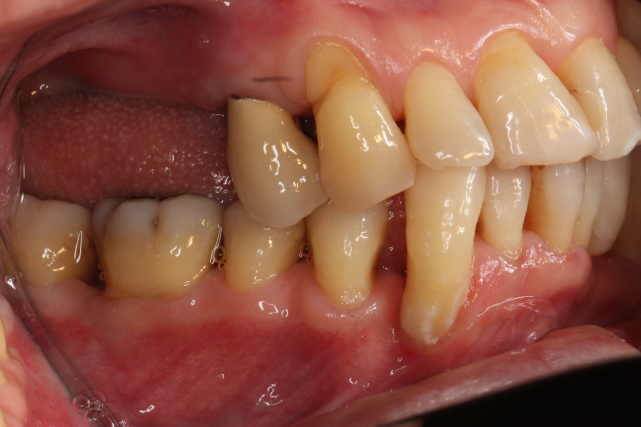

短縮歯列治療後の写真

数年前、上の奥歯を重症の歯周病で抜歯。その後、専門医の治療を希望し当院を受診。治療後の定期健診を受けている。上の奥歯がないが、食べることに問題ないため、このまま経過観察。残った歯の管理、特に噛み合わせのチェックに注意しながら見守っている